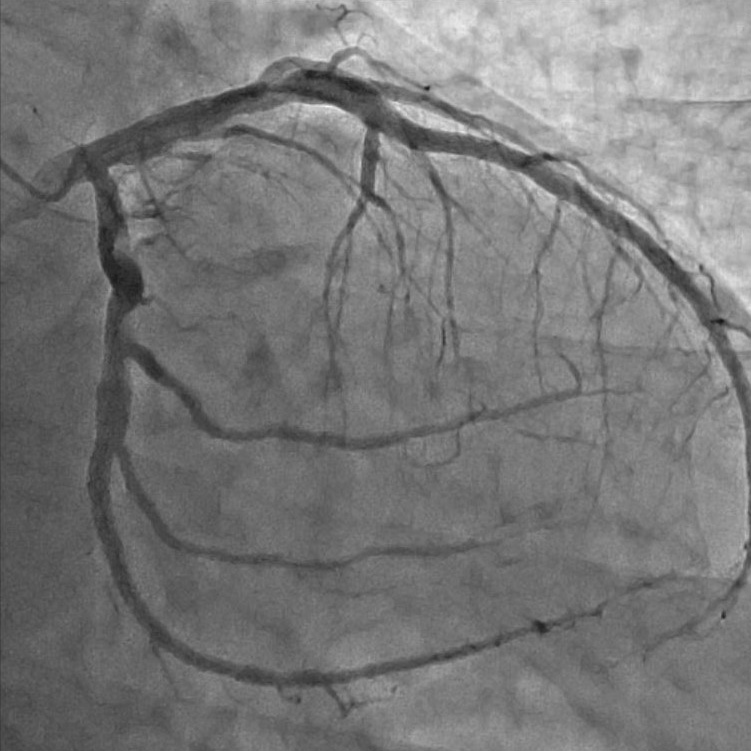

血管造影室:Alphenix (Canon)

血管造影装置は、X線TV室で使用している装置同様、X線を使ってリアルタイムで体内の情報を確認しながら手術を行う際などに使用する装置です。X線TV室と異なるのは血管造影に使用する点で、装置を動かすことによって患者さんの体の向きを変えずに、さまざまな方向から見れるような作りになっています。

血管造影とは、カテーテルと言われる細い管のようなものを、手首または足の付け根の動脈から血管内に挿入して、目的部位まで進め、造影剤を注入することで血管が描出されます。

放射線技師は主に装置の管理や画像の管理、被ばく線量の管理をしています。

- 当院での主な使用 ・心臓の血管の検査・治療(心臓カテーテル検査・治療)